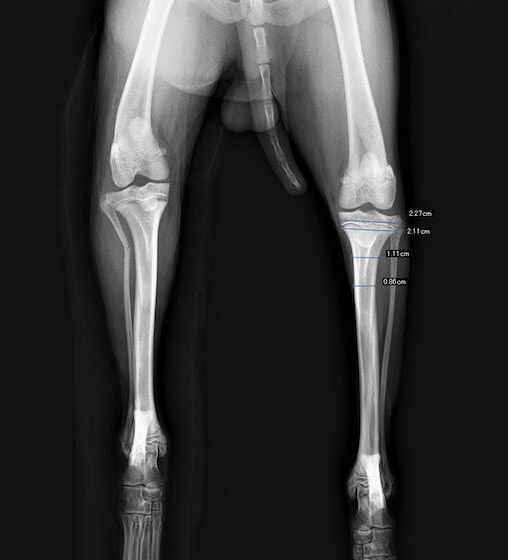

ペルシャ猫 11ヶ月齢 雄

他院にて左大腿骨遠位の成長板骨折(salter-harrisⅠ型)が認められており、治療相談を目的として来院。当院にて、キルシュナーワイヤーを用いたピンニングにより骨折部位の整復を行いました。術後の経過は良好で、現在も経過観察中です。

術前レントゲン